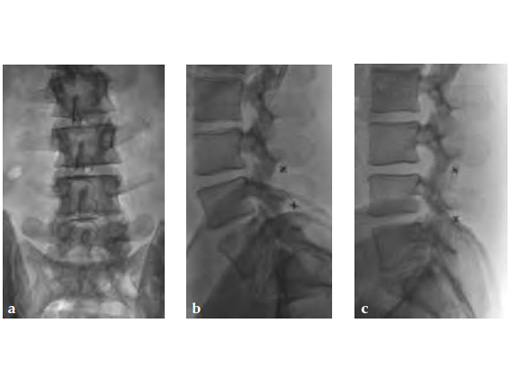

For the percutaneous approach, a guide wire is inserted to the spinal level that needs to be distracted. Next, distractors are placed sequentially one over the other until adequate distraction is reached. Finally, the implant is inserted and wings are deployed to help keep the implant in place.

With the posterior, mini-open approach, muscles only need to be stripped unilaterally, therefore it is less invasive than some competitors bilateral approach. Trial distractors are placed sequentially one after the other until adequate distraction is reached. The final step, as with the lateral approach, is to insert the implant and deploy the wings.

Both surgical approaches are aided by x-ray imaging, to better visualize proper placement of the in-space. Unlike standard decompression surgery, in-space does not require the removal of any bone and supporting ligaments remain uncompromised. Thus, spinal stability is not affected by the procedure.